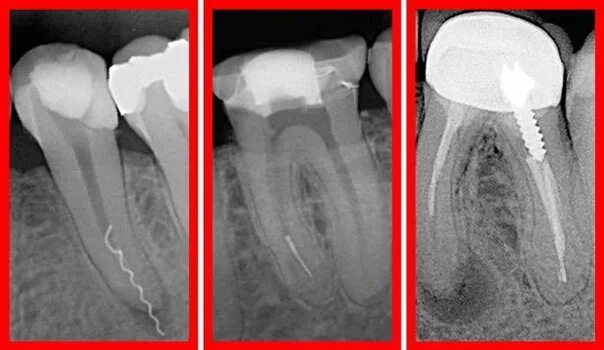

Пломбирование перфорации